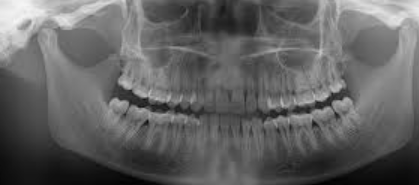

FMX